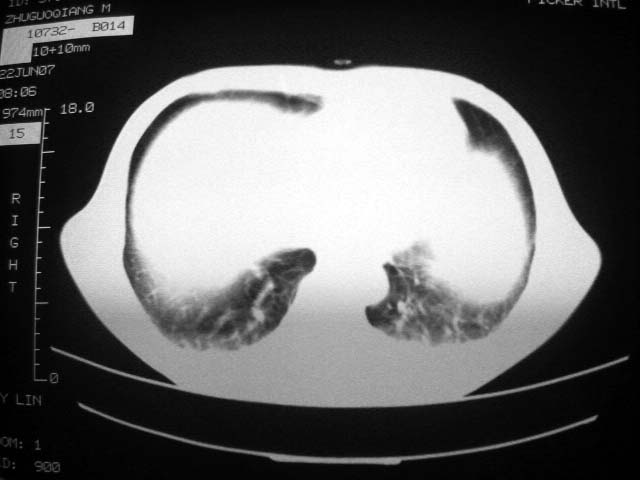

从ct7988c 至今未用任何抗生素及抗痨药,维持保肝治疗。患者低热、咳血渐消失。

07年6月22号复查

前几次大家认为是转移癌,但此次复查病灶却明显吸收好转,不支持诊断。请大家讨论。[emb10]

bu不可思议,前三次都怀疑转移,但从这次的片子看仍有结节,就是比原来小

双侧继发性肺结核伴两肺播散灶.双侧胸腔少量积液

近2个月病灶变化较大,应是感染性病变,首先考虑金黄色葡萄球菌感染。

根据前后片比较应该考虑迁徙性肺脓肿,回帖相差甚远是因为前后片变化太大出乎大家意料之外,这就是影象诊断要结合临床复查对比的必要性,

回顾既往片,病变明显吸收,缩小,未经治疗,不支持肺转移瘤,可能为肺结节病或韦格氏肉芽肿